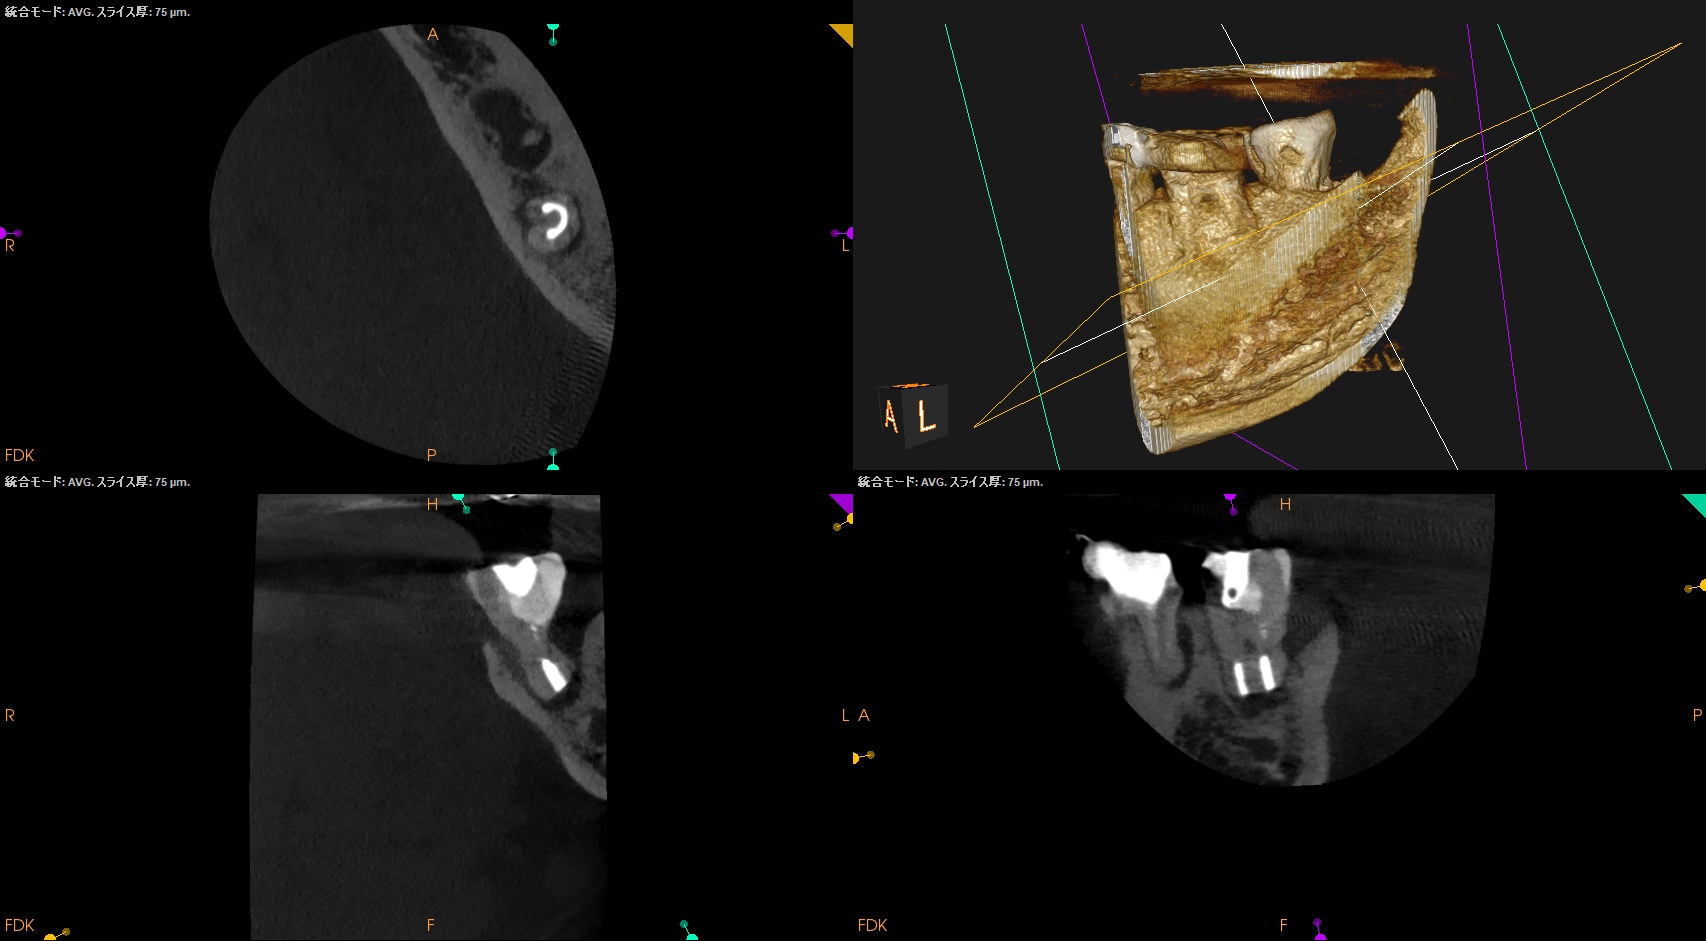

CBCT(2025.12.10)

D

遠心方向から見ると、

絶望的な状態であることがわかる。

PA, CBCTを撮影した。